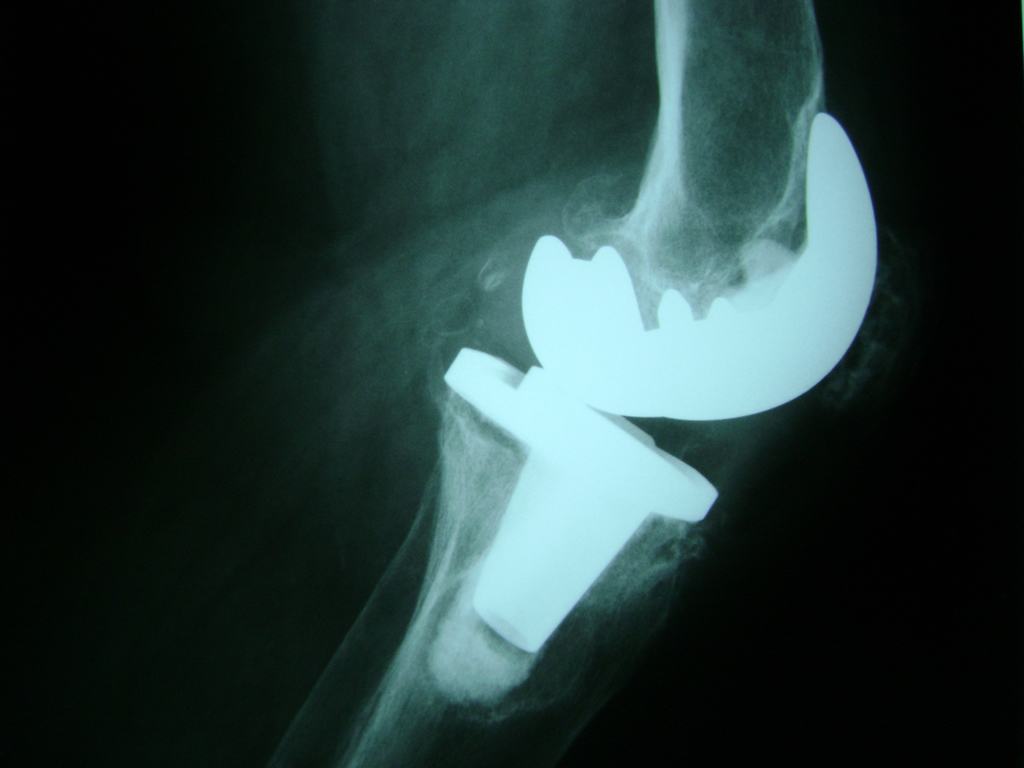

Cirugías de Calcaneo - Rodilla

La artroscopia de rodilla es un cirugía en el cual la estructura interna de la articulación es examinada ya sea para realizar un diagnostico o para realizar un tratamiento, este procedimiento se realiza utilizando un instrumento parecido a un pequeño tubo llamado artroscopio.